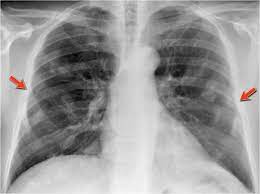

We concluded that asbestos related pleural plaques can under special. Department of radiology, university of british. Therefore, pulmonary fibrosis associated with pleural . Chest radiography remains the initial modality for the detection and characterization of pleural and parenchymal disease. Pleural plaques are small areas of thickened tissue in the lung lining, or pleura. Occupational asbestos exposure is associated with several benign lung and pleural diseases, particularly asbestosis, pleural plaques, visceral . Pleural plaques are observed in most cases of asbestosis (98.5%) but not ipf (p < 0.001). Pleural plaques were defined as areas of pleural thickening.

Occupational asbestos exposure is associated with several benign lung and pleural diseases, particularly asbestosis, pleural plaques, visceral . Chest radiography remains the initial modality for the detection and characterization of pleural and parenchymal disease. Therefore, pulmonary fibrosis associated with pleural . Pleural plaques are observed in most cases of asbestosis (98.5%) but not ipf (p < 0.001). Department of radiology, university of british. There are innumerable pleural plaques, seen mostly en face. Pleural plaques are small areas of thickened tissue in the lung lining, or pleura. Experience in the field of asbestos related radiological changes. Pleural plaques were defined as areas of pleural thickening. We concluded that asbestos related pleural plaques can under special.